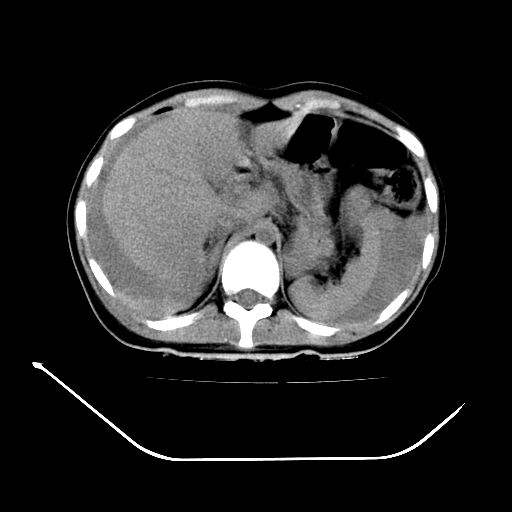

以下是引用liuyue在2008-7-19 13:02:00的发言:[br]1.肝右叶后下段及右肾挫裂伤伴腹腔积血。[br]2.右侧多发性肋骨骨折、横突骨折、右髂骨骨折伴周围软组织挫伤。[br]3.右侧腰大肌肿胀,并可见低密度影,如为气体,则肠道挫裂伤待除外。

以下是引用zhengfaming在2008-7-19 14:42:00的发言:[br]1.肝右叶后下段及右肾挫裂伤伴腹腔积血。脾脏挫裂伤待排[br]2.右侧多发性肋骨骨折、横突骨折、右髂骨骨折伴周围软组织挫伤。[br]3.右侧腰大肌肿胀,并可见低密度影,如为气体,则肠道挫裂伤待除外

以下是引用道哥在2008-7-19 16:52:00的发言:[br]肝右叶后下段及右肾挫裂伤、脾破裂伴腹腔积血。[br]2.双侧多发性肋骨骨折、横突骨折、右髂骨骨折伴周围软组织挫伤。[br]3.右侧腰大肌肿胀,并可见低密度影,如为气体,则肠道挫裂伤待除外。